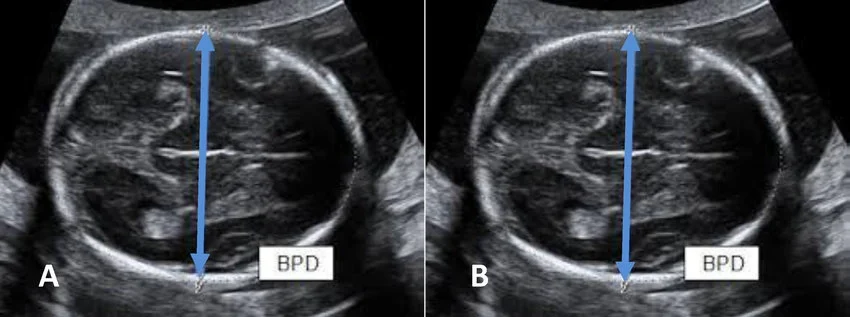

Tật đầu nhỏ thai nhi (Microcephaly)